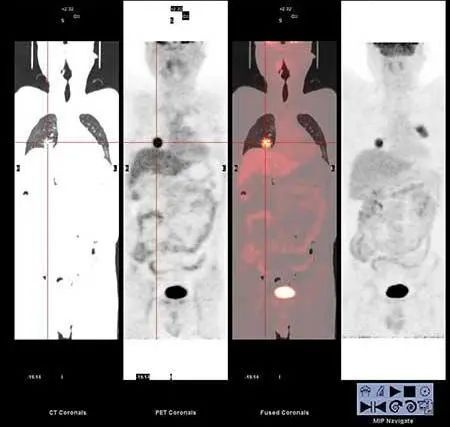

全身正电子发射断层成像(PET)检查在无症状复发病灶诊断上有较高的敏感度及特异性。当一些良性病变(如肺不张、肺实变和放射性纤维化)在标准CT影像中难以与肿瘤区分时,全身PET-CT或PET-MR可以区分真正的恶性肿瘤,因此可根据患者病情、意愿、经济能力等做出选择。